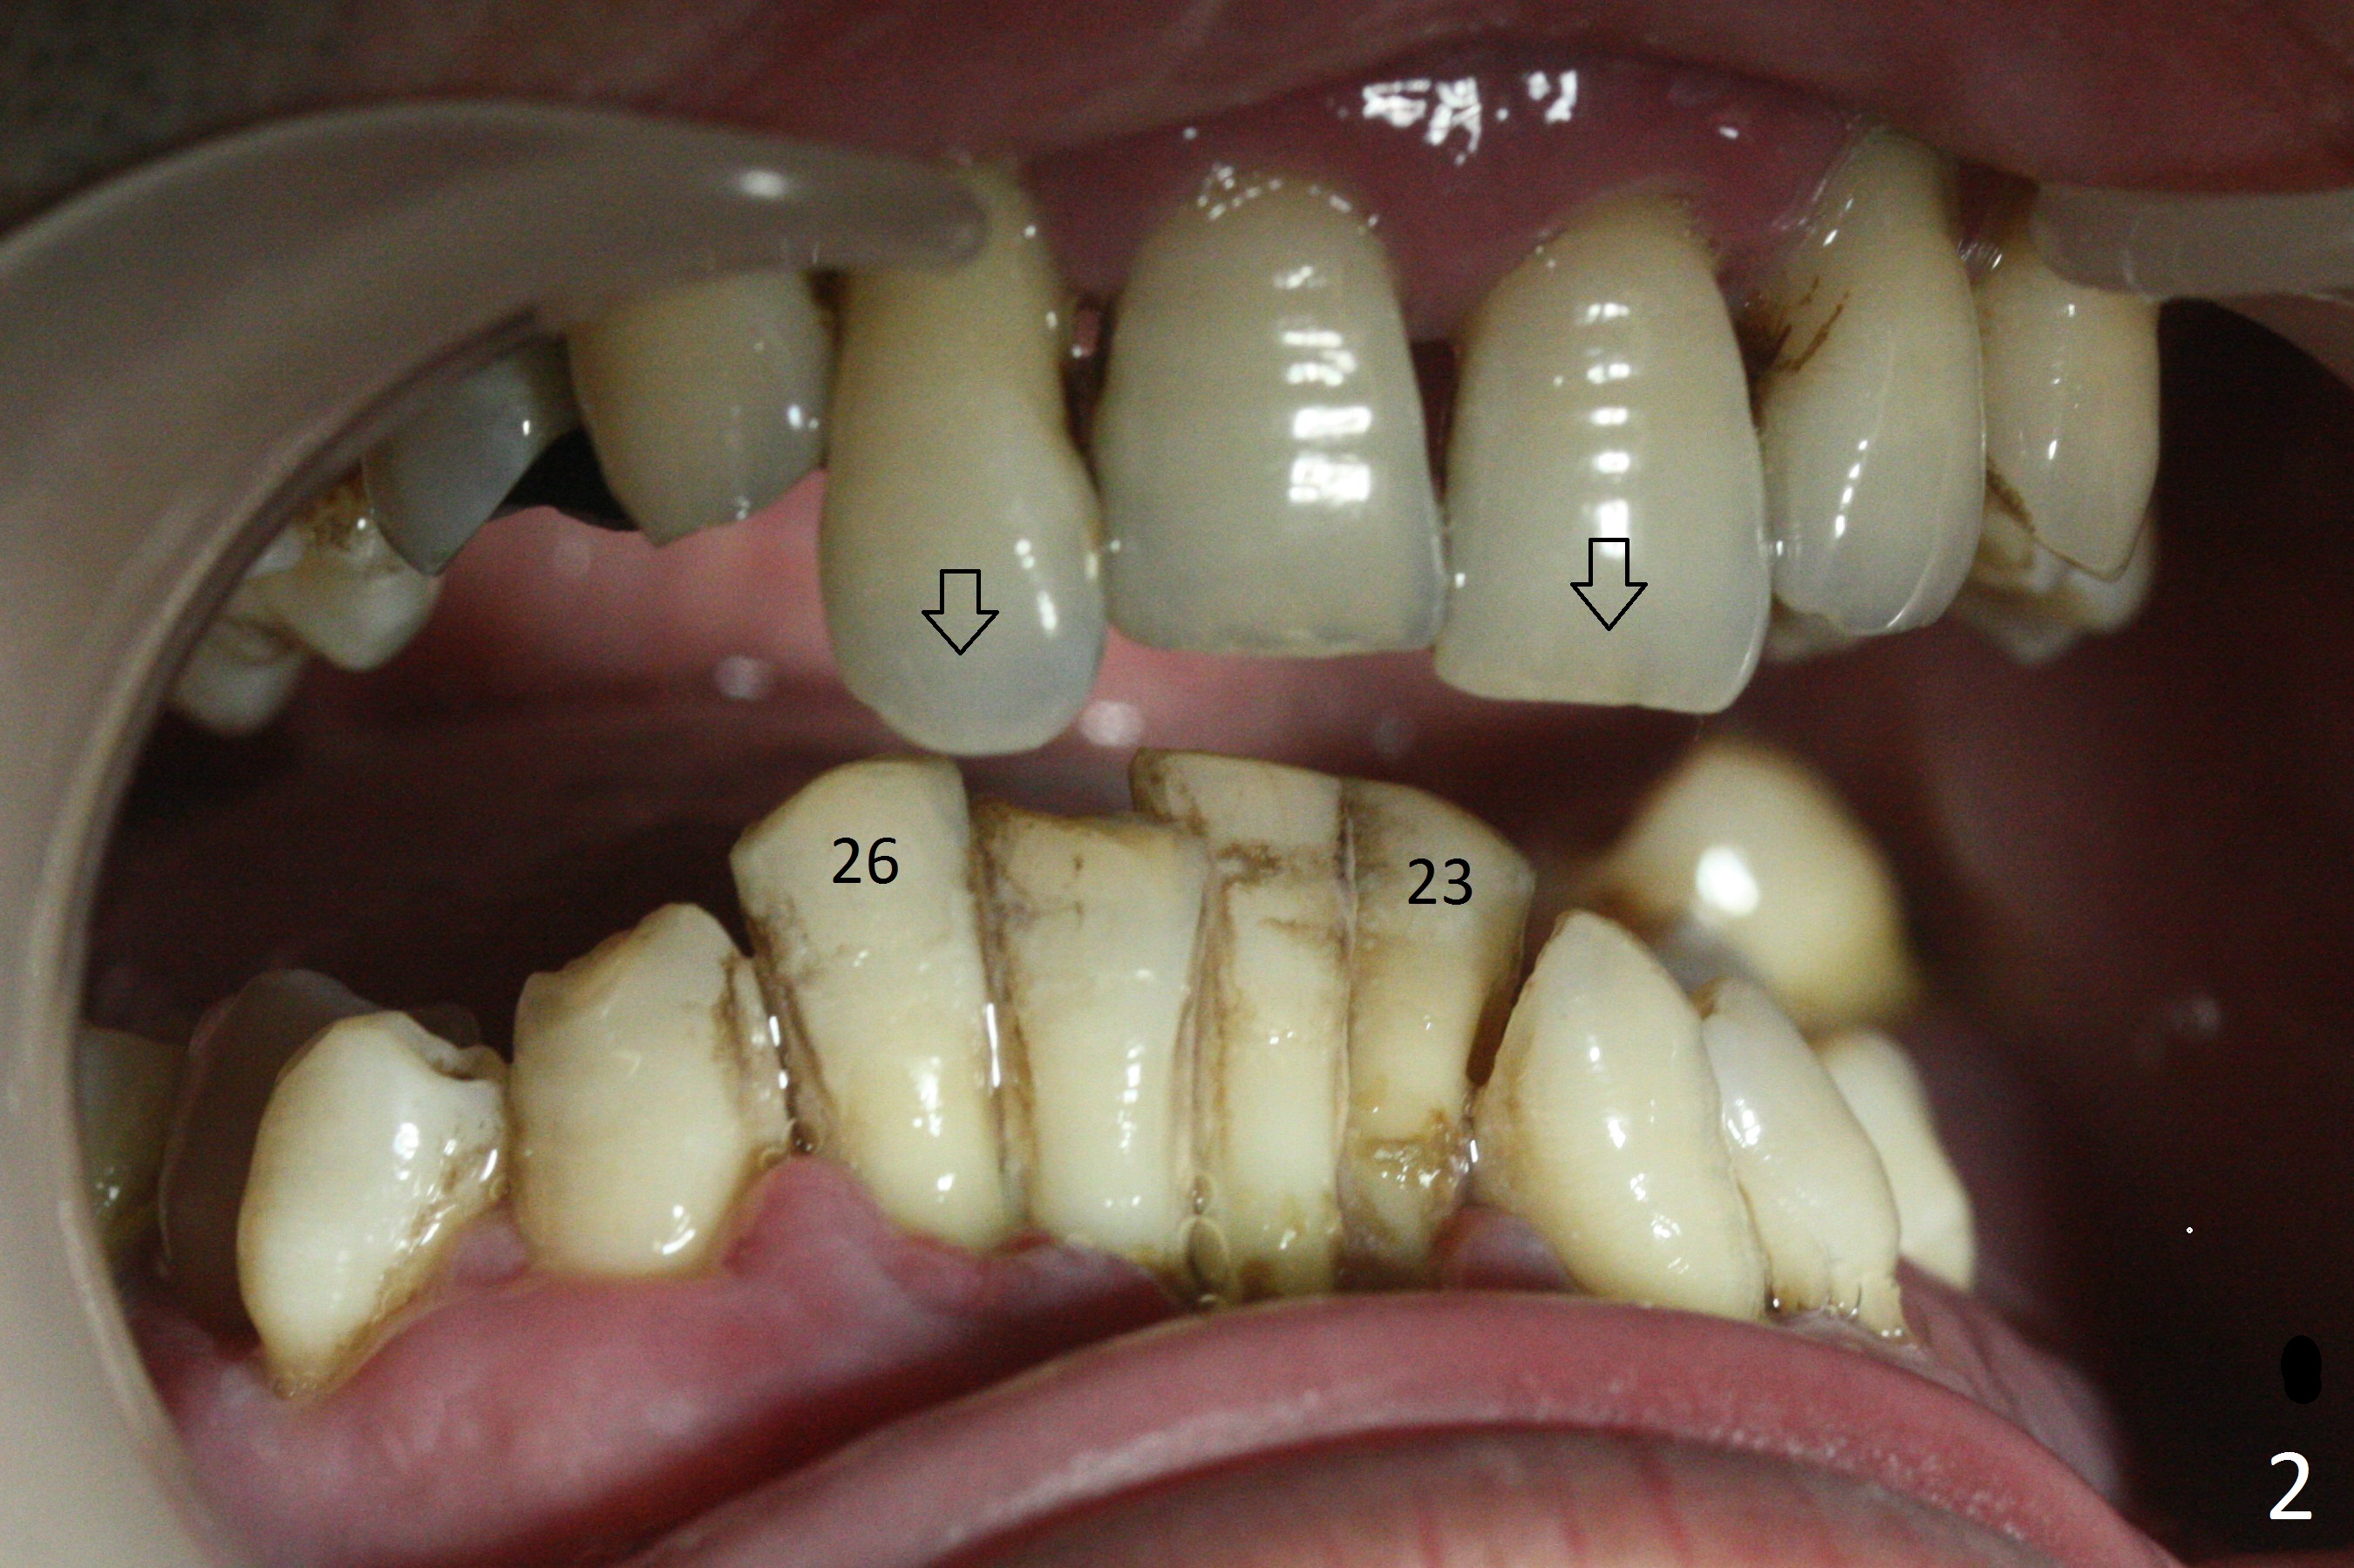

A 36-year-old man (ex-smoker) has advanced chronic periodontitis (Fig.1-5). His chief complaint is "I cannot chew on the right side now because of pain (Fig.1: #3 abscess <) and the bottom front teeth are loose (Fig.2,5: #23-26)". He has not masticated on the left side because of the mobile teeth. Due to finance, implants will be placed at #3,4 (Fig.12), 23 and 26 at the appointments of scaling & root planing.

Class II Division II malocclusion (Fig.2,6) will make it difficult to restore #23-26 implant-supported FPD. Although the teeth #7-10 may need to be replaced later (Fig.7,8), enameloplasty will be conducted for #7-10 (Fig.9 white area; Fig.12 black circles (gross reduction)) prior to #23-26 extraction and implant placement (Fig.10). To be flexible in restoration (angulation) and possible future hybrid denture, 2-piece narrow implants will be placed (3.0 or 3.3 mm) instead of 1-piece ones. In fact CBCT shows that the narrowest regular implant (3.8 mm) can be placed in the lower anterior region (Fig.13-15).